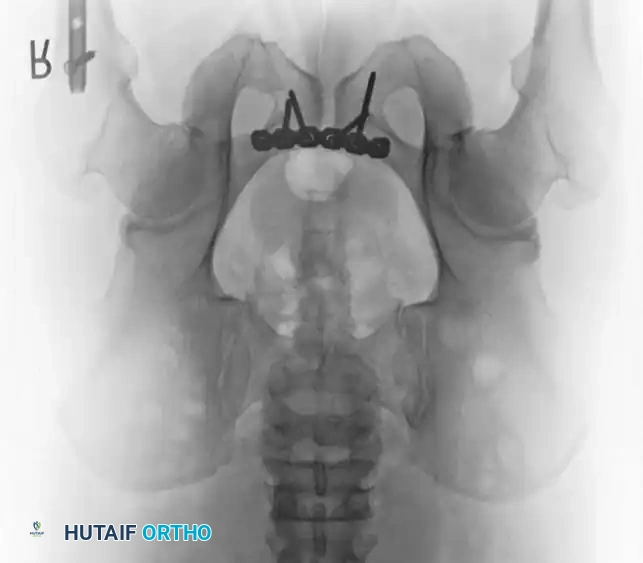

3. Percutaneous Sacroiliac (SI) Screws (Posterior Ring)

The gold standard for posterior ring fixation in appropriately selected patients.

* Indications: Sacral fractures, SI joint disruptions, crescent fractures.

* Technique: Performed under strict fluoroscopic guidance (Inlet, Outlet, and Lateral sacral views).

* Trajectory: The guide wire is advanced from the lateral ilium, across the SI joint, into the S1 (or S2) vertebral body.

* Safety Corridors: The surgeon must possess an intimate understanding of sacral dysmorphism. The "safe zone" is bounded by the sacral neural foramina inferiorly, the spinal canal posteriorly, and the sacral ala anteriorly.

Pitfall: Failure to recognize a dysmorphic sacrum (characterized by upper sacral segment elevation, non-recessed alae, and oblique neural foramina) can lead to catastrophic L5 nerve root injury or vascular penetration during SI screw placement.

Image